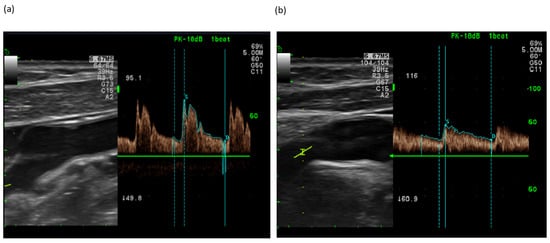

2.5.2. Doppler Ultrasonography (CA and BP)

3.2. Changes in BP and CA Velocity